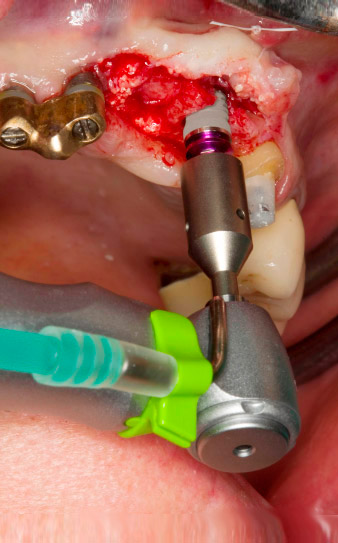

Después de la cicatrización primaria, los tejidos blandos se modelaron con ayuda del puente con base reconstruida. Dos meses después, se procedió a la exposición del área con una incisión de la cresta maxilar en sentido ligeramente palatino (figura 2).

El hueso alveolar de la posición 22 resultó tener unas dimensiones suficientes. Las figuras 2 y 4 muestran la preparación del lecho del implante, el corte de rosca y la colocación del implante con el equipo Implantmed.

El nuevo motor para implantología se utilizó siempre con los contra-ángulos quirúrgicos adecuados de W&H.